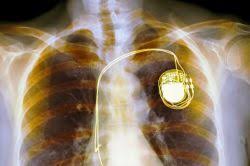

*Σχετικά με πιθανή δυσλειτουργία ενός εμφυτευμένου νευροδιεγέρτη DBS που έφερε ο πατέρας μου ασθενής Παρκινσον

-Ο δεύτερος ήταν η συνειδητοποίηση ότι δεν μας είχαν δώσει ποτέ το σωστό εγχειρίδιο χρήσης. Επιπλέον διαπίστωσα ότι ο ΕΟΦ απέκρυπτε σοβαρές ανακλησεις και ενημέρωση που αφορούσαν το προϊόν που είχε εμφυτευτεί στον ασθενή